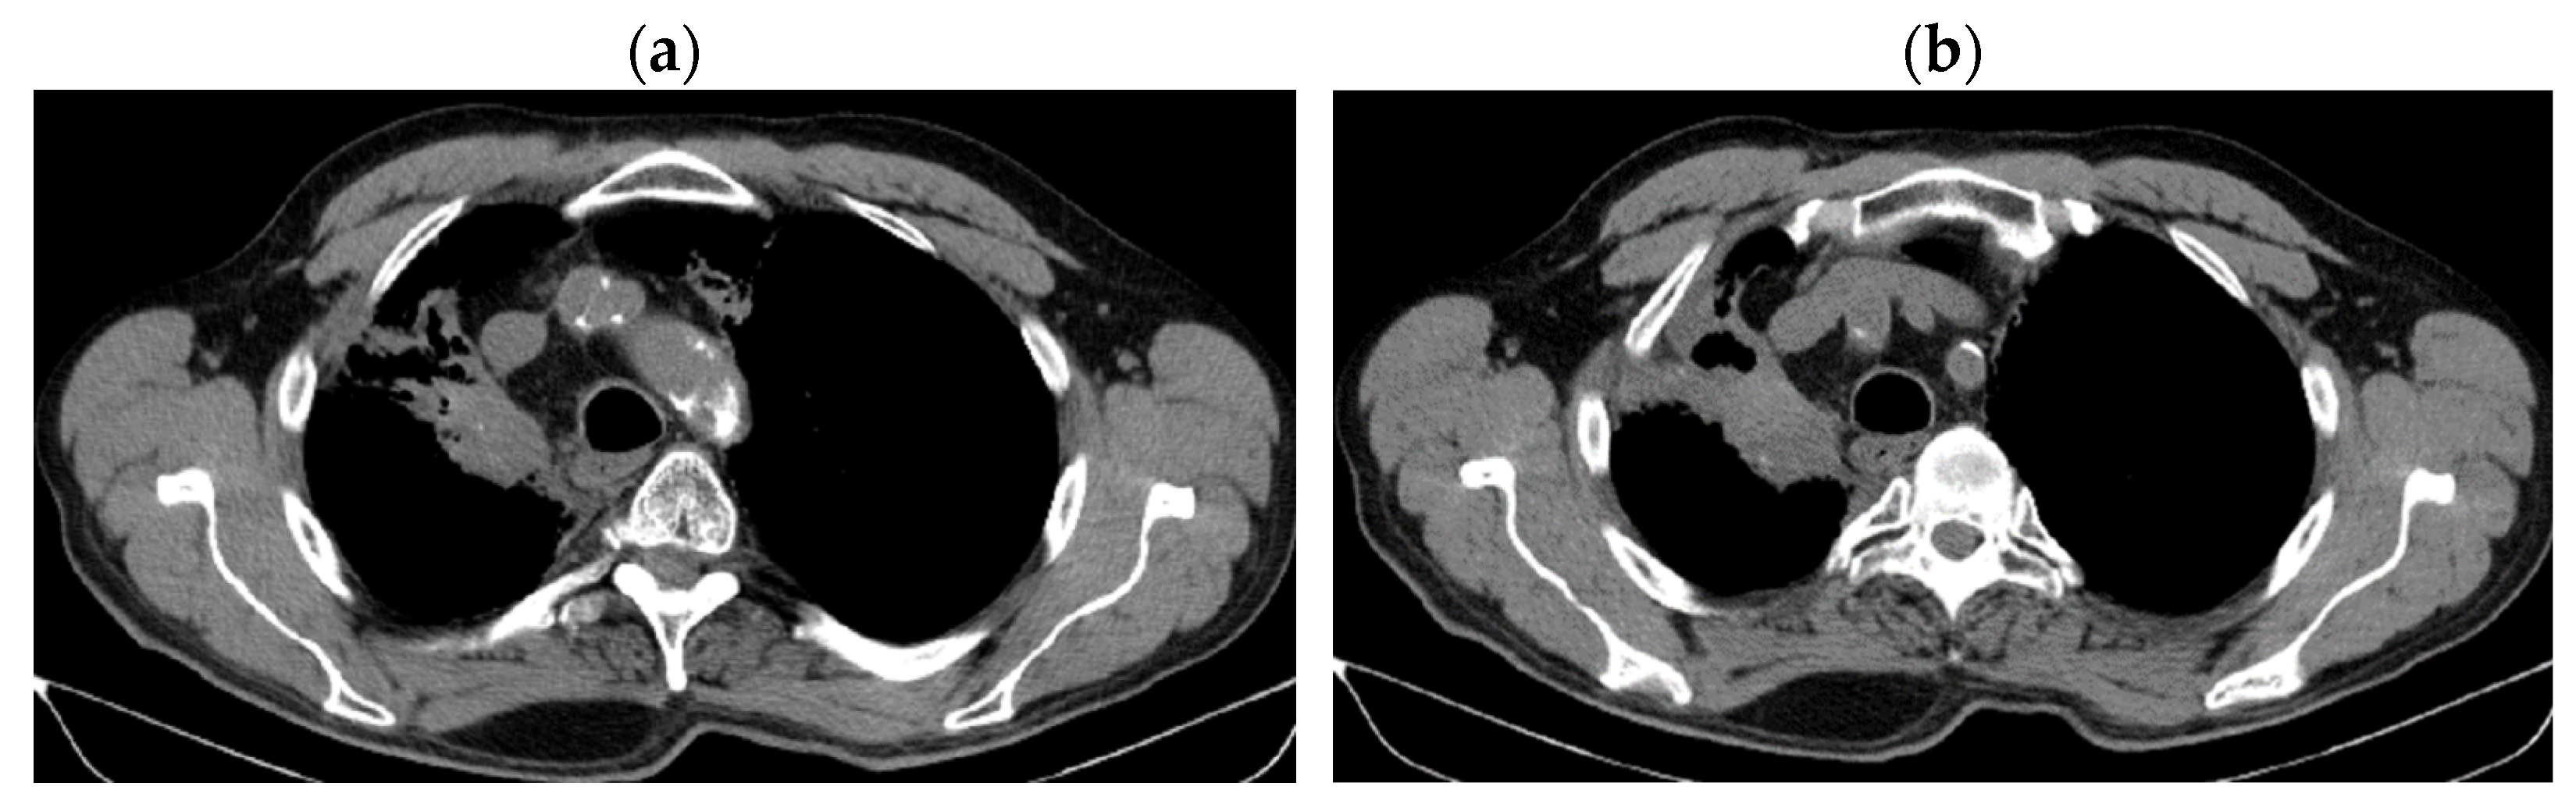

2. Case Presentation

2.2. Monitoring 2022: Oncological Commission 1910/16.08.2022

2.3. Oncological Committee 07/25/2023 Recommended

3. Case Results